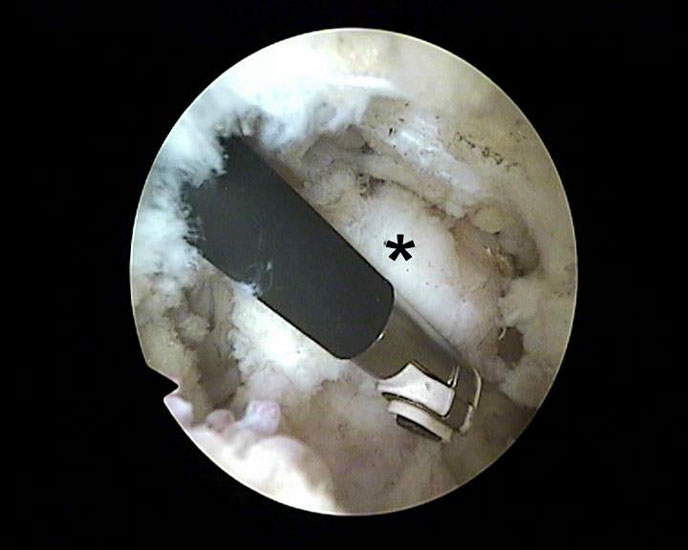

Abbildung Nr. 8-10

Es wird zunächst ein Weichteildebridement durchgeführt, bis die Flexor hallucis longus-Sehne identifiziert werden kann. Während des Debridements sollte auf die korrekte Ausrichtung der Instrumentenöffnung nach lateral geachtet werden. Im Verlauf empfiehlt sich der Wechsel auf eine bipolare Ablationselektrode, die eine gezielte Freilegung der Strukturen unter gleichzeitiger Blutstillung ermöglicht, ohne dabei unkontrolliert Gewebe anzusaugen (rechte Seite, m=medial, l=lateral). Das Os trigonum bzw. die Osteophyten sowie die FHL-Sehne müssen vollständig dargestellt werden (*=Os trigonum, FHL=Flexor hallucis longus-Sehne).